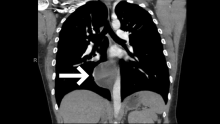

This is a case of a twenty-nine-year-old woman who initially presented to the emergency department with right-sided pleuritic chest pain, syncope, and leukocytosis. A CT angiogram revealed bilateral segmental and subsegmental lower lobe pulmonary emboli, as well as an indeterminate round posterior mediastinal mass measuring approximately 6 cm in its largest diameter and located just right of the midline, adjacent to the esophagus. The patient was scheduled for a right-sided video-assisted thoracoscopic surgery (VATS) for resection of the posterior mediastinal mass vs. cyst after three months of anticoagulation was completed for the treatment of her pulmonary emboli.